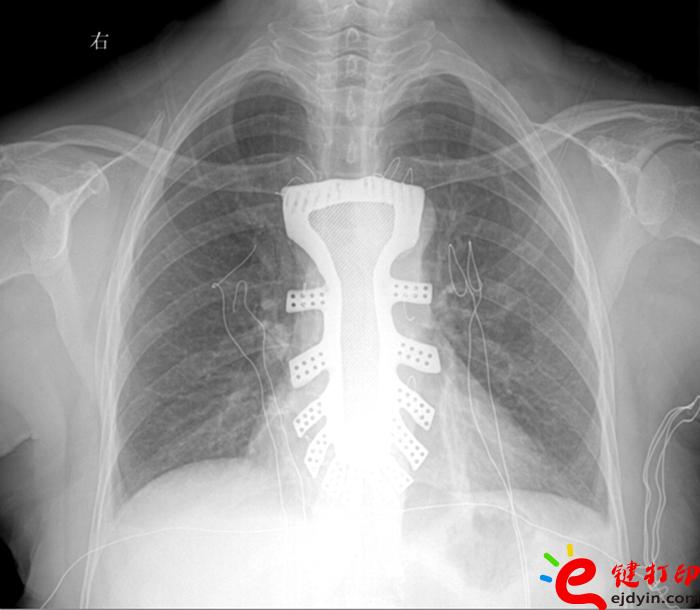

“手术历时2.5小时,对患者的胸骨进行了整体切除,置换了钛合金胸骨,目前患者恢复良好,未发现任何并发症。”王小平教授称,根据专业机构检索,该手术是世界首例针对胸骨肿瘤疾病,将3D打印的可植入性钛合金胸骨植入人体,实现病变胸骨的整体置换的手术。该手术的成功意味着未来将会为更多的胸骨肿瘤患者带来福音。

据王小平教授介绍,唐都医院3D打印小组经过精密计算患者胸骨的大小、形状等,充分研究讨论,历时一周,为患者设计出了手术使用的3D胸骨模型,并与西北工业大学凝固技术国家重点实验室合作,为患者打印出了1:1钛合金胸骨模型。随后,又对该模型进行了一系列严密的医学处理。